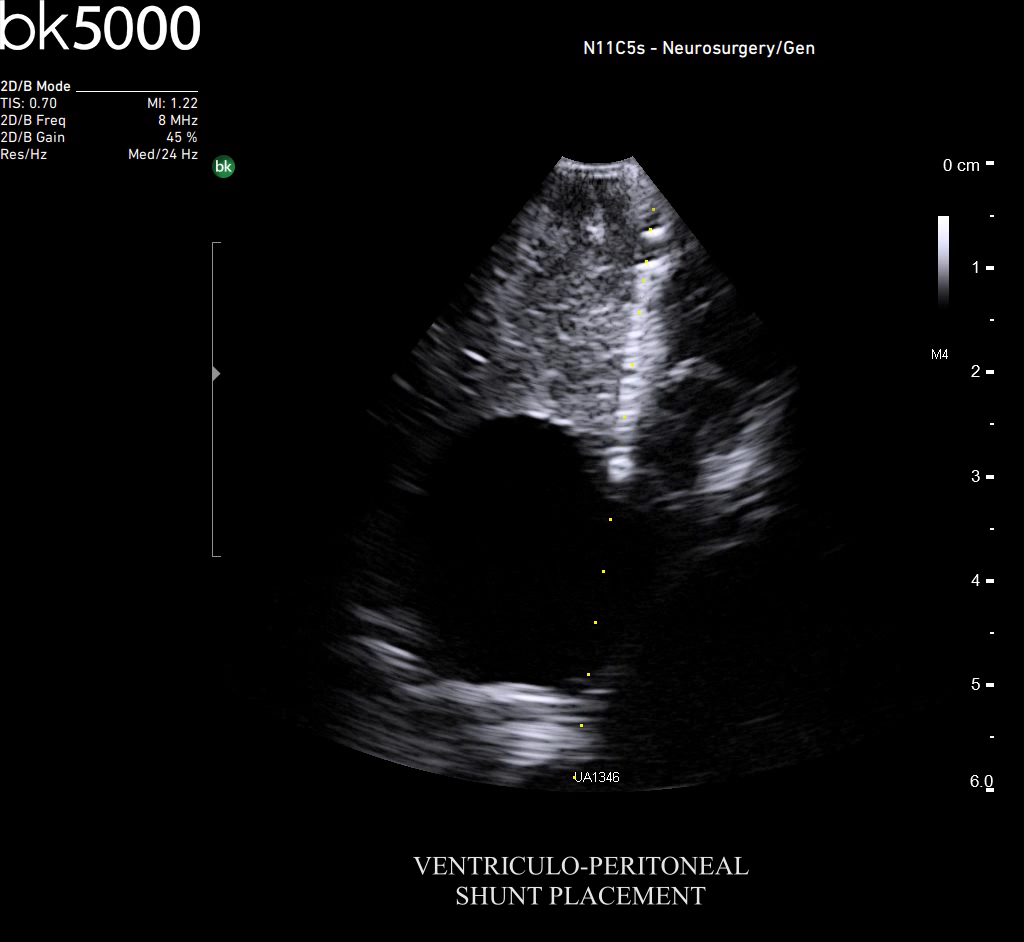

Ultrasound can improve neurosurgical procedures by helping you navigate and identify lesions and anatomical structures in real-time. This is particularly important as the data obtained from a preoperative CT or MRI scan can be outdated at the time of surgery. The bk5000 neurosurgical system provides the highest quality images that allow you to clearly see the margins of a lesion and to determine the best course of action. Using advanced graphics processing technology, this powerful system provides immediate, auto-optimized images that allow you to see the information you need, faster.

Transducers designed for Neurosurgery

The specialized, high-resolution, sterilizable neurosurgery transducers enable you to obtain detailed images of the brain and spinal cord. They have a convenient Smart™ button that lets you activate the transducer, then freeze, store or print the images at the press of a button. Disposable, easy-to-use needle guides assist with targeting lesions.

*Burr-Hole Transducer (N11C5s) has been cleared for adults and children (>2 - 12 years).